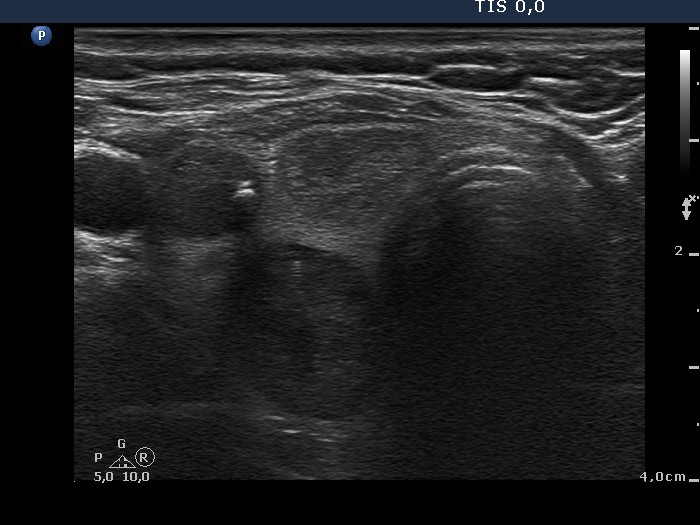

Third examination 4 years after initial examination (4th row of images)

Summary of follow-up: the patient underwent yearly ultrasound examination. She had no complaints.

Functional state: euthyroidism with TSH-level mIU/L.

Ultrasonography: the ultrasound presentation of the thyroid was unchanged except for an increase in nodule volume.

Surgery was advised but the patient asked us to go on follow-up examinations

A left lobectomy was performed and histopathology disclosed follicular adenoma and Hashimoto's thyroiditis in the extranodular part.